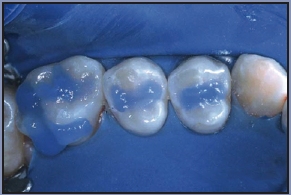

Figure E

Figure F